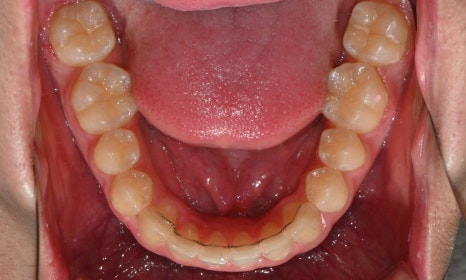

2024.12. 초진 구내사진 - 연세정원치과

정밀 검진 결과, 하악 치열이 좌측으로 틀어져 있었고 그로 인해 위아래 치아 중심선이 일치하지 않았습니다. 아래 치열이 전체적으로 전방 위치하여 아래 입술 돌출이 더 도드라져 보이는 상태였습니다. 그리고 상악궁이 하악궁보다 좁아서 앞니 부위 일부 반대로 물리는 치아 교합도 관찰되었습니다. 특히 외상 치아의 경우, 교정력 적용시 추가적인 염증성 치근 흡수 위험이 존재하기 때문에, 치료 중 지속적인 관찰이 필수적인 상황이었습니다.